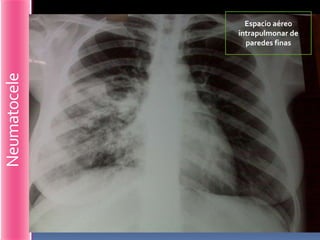

Espacio aéreo

intrapulmonar de

paredes finas

Neumatocele

Espacio aéreo intrapulmonar de paredes finas Neumatocele